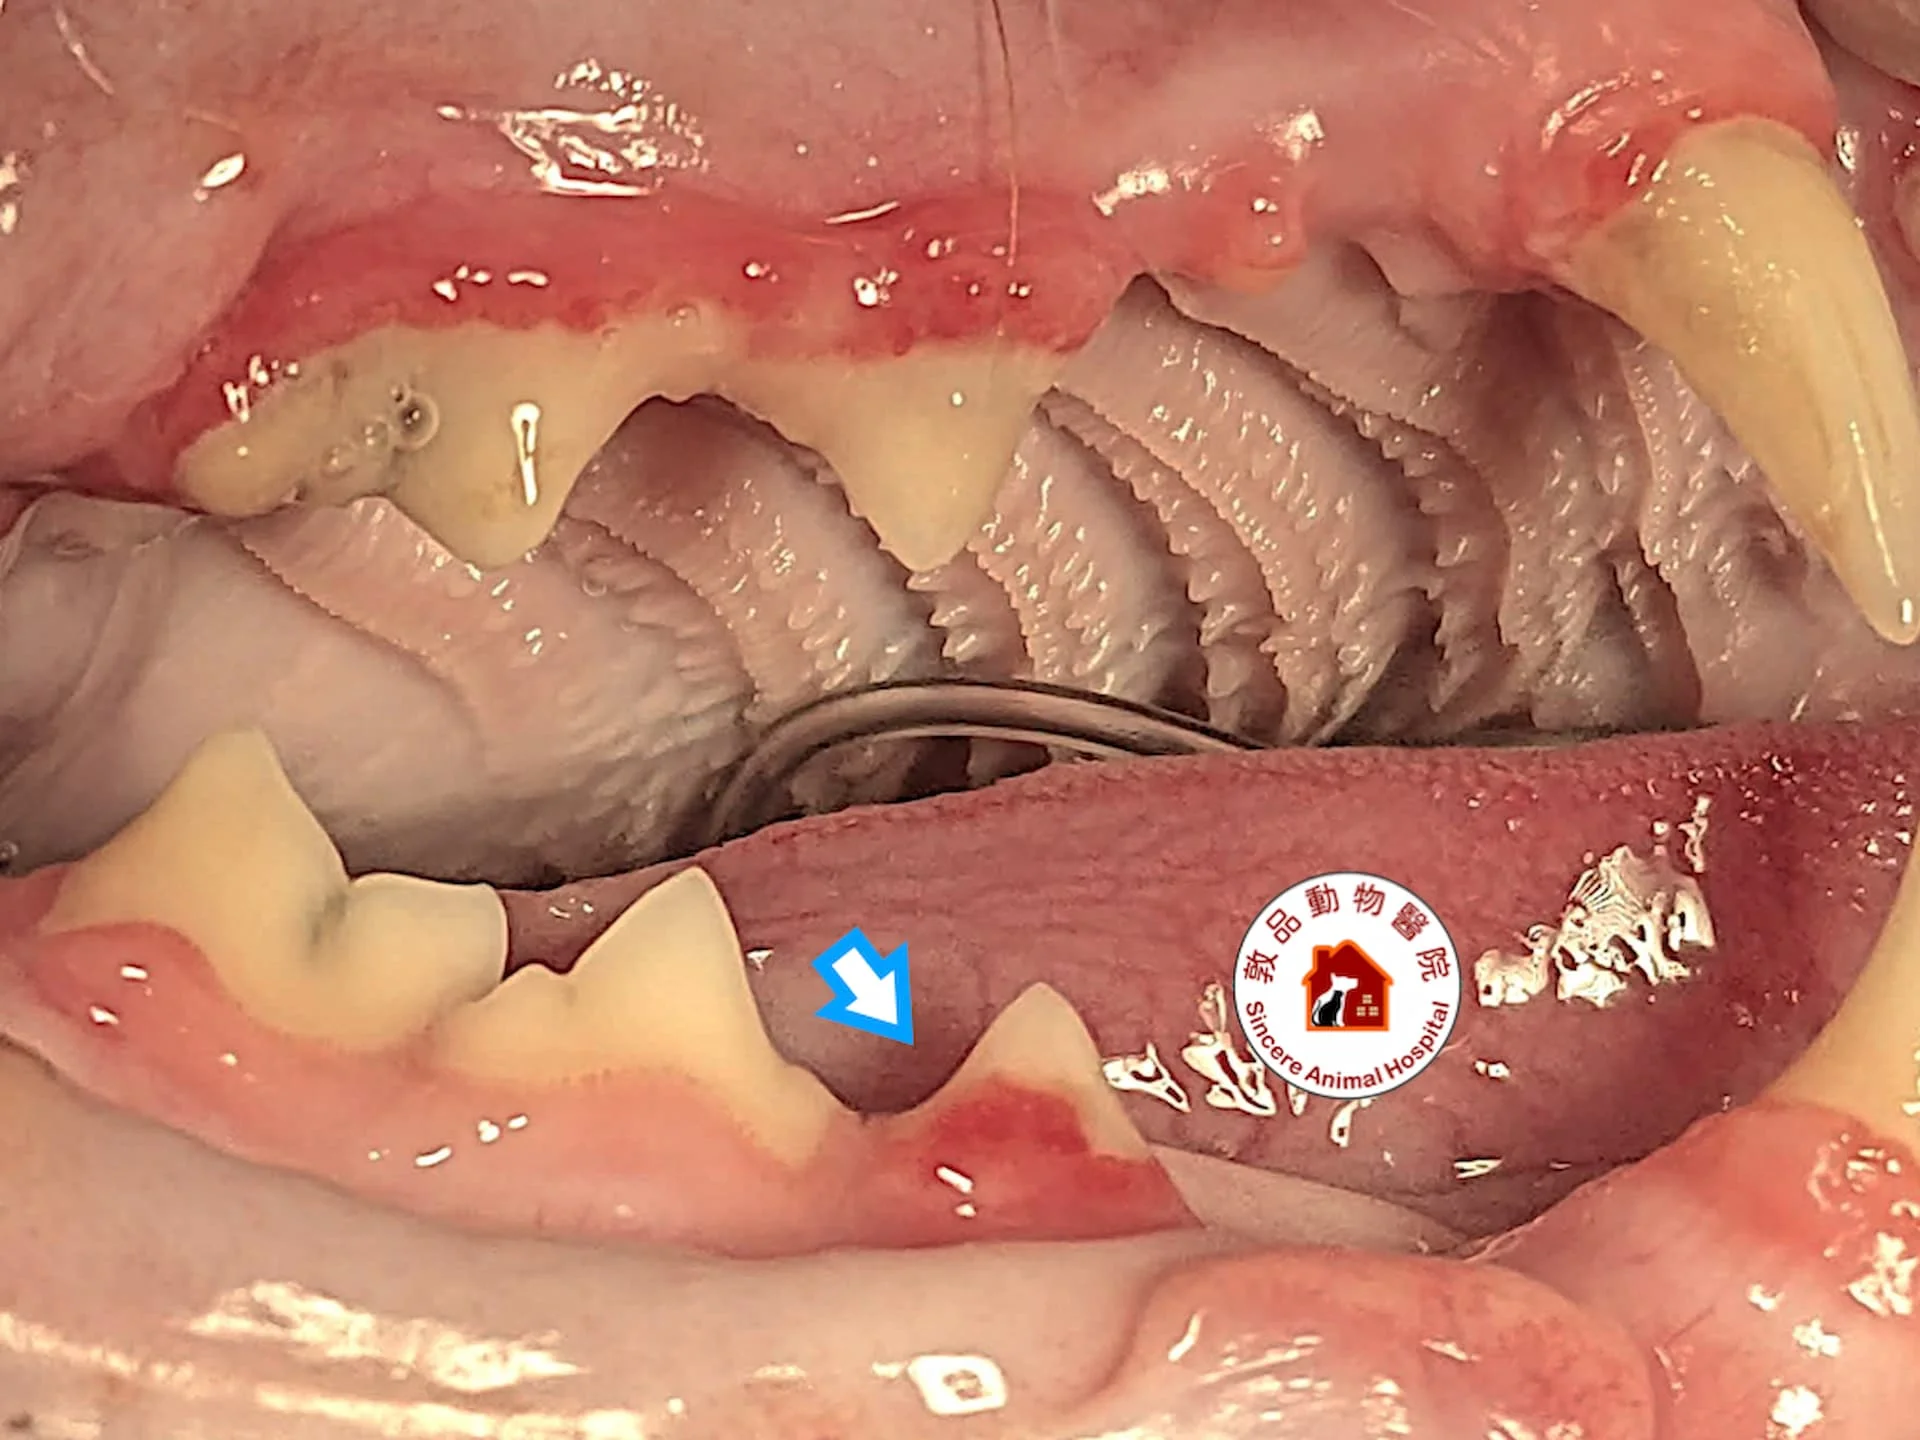

圖片中可以明顯見到上下排牙齒破裂情況

貓齒吸收疾病常見樣貌

貓齒吸收疾病初期,只會看到牙齦往牙齒上生長

觸碰會有疼痛感